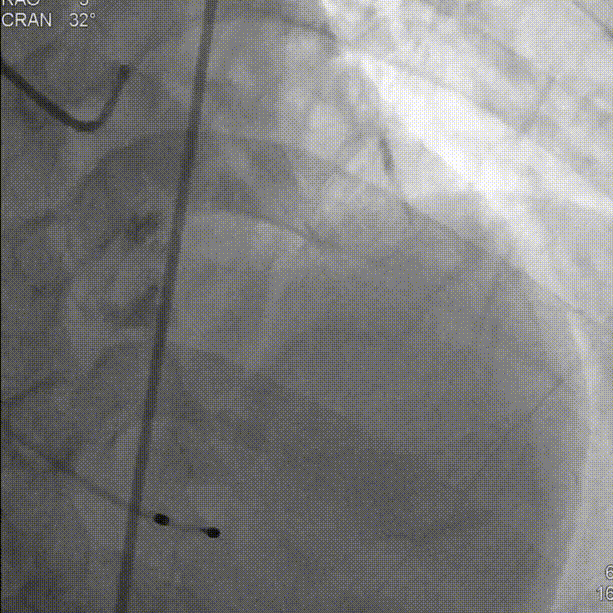

直头导丝跨瓣:

初始定位,左右窦重叠视图开始释放:

释放中期,快速起搏下释放到80%切换视图,并借助食管心超评估深度和反流情况: